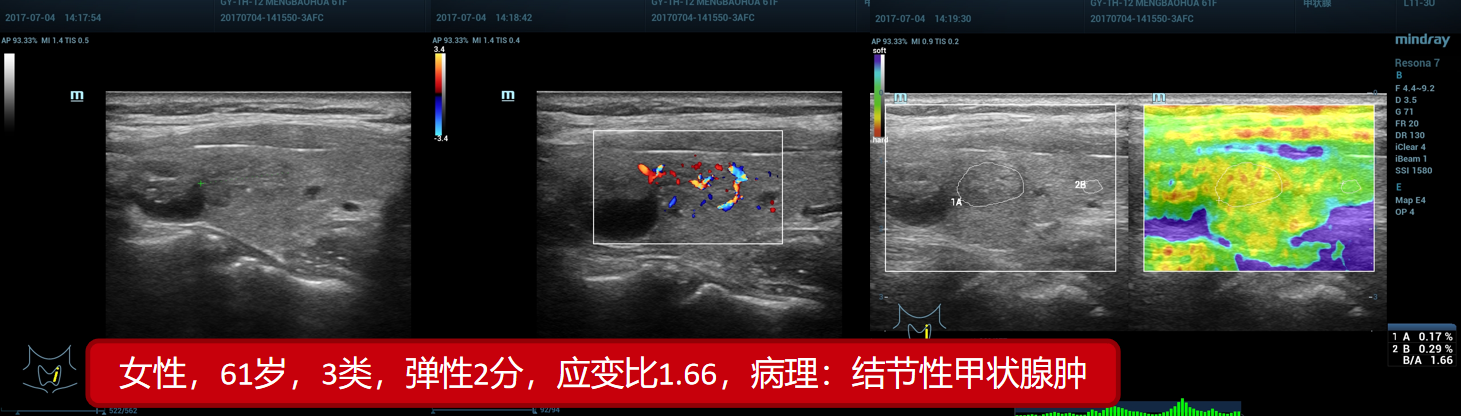

6、结节性甲状腺肿(贵州医科大附属医院)

6、结节性甲状腺肿(贵州医科大附属医院)